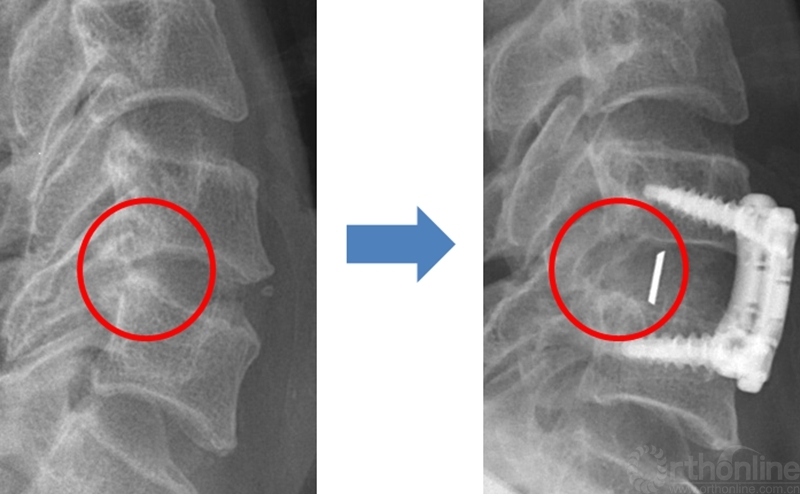

显微镜下对颈椎的骨、韧带、硬脊膜之间的组织辨识度增高,结合磨钻增加了潜行减压去除椎间隙后缘骨赘的安全程度,术中可以在撑开的椎间隙的情况下,使用磨钻从椎体前缘平行打磨上下终板至后纵韧带层面,实现上下椎体后缘骨赘的满意去除。

潜行减压去除骨赘